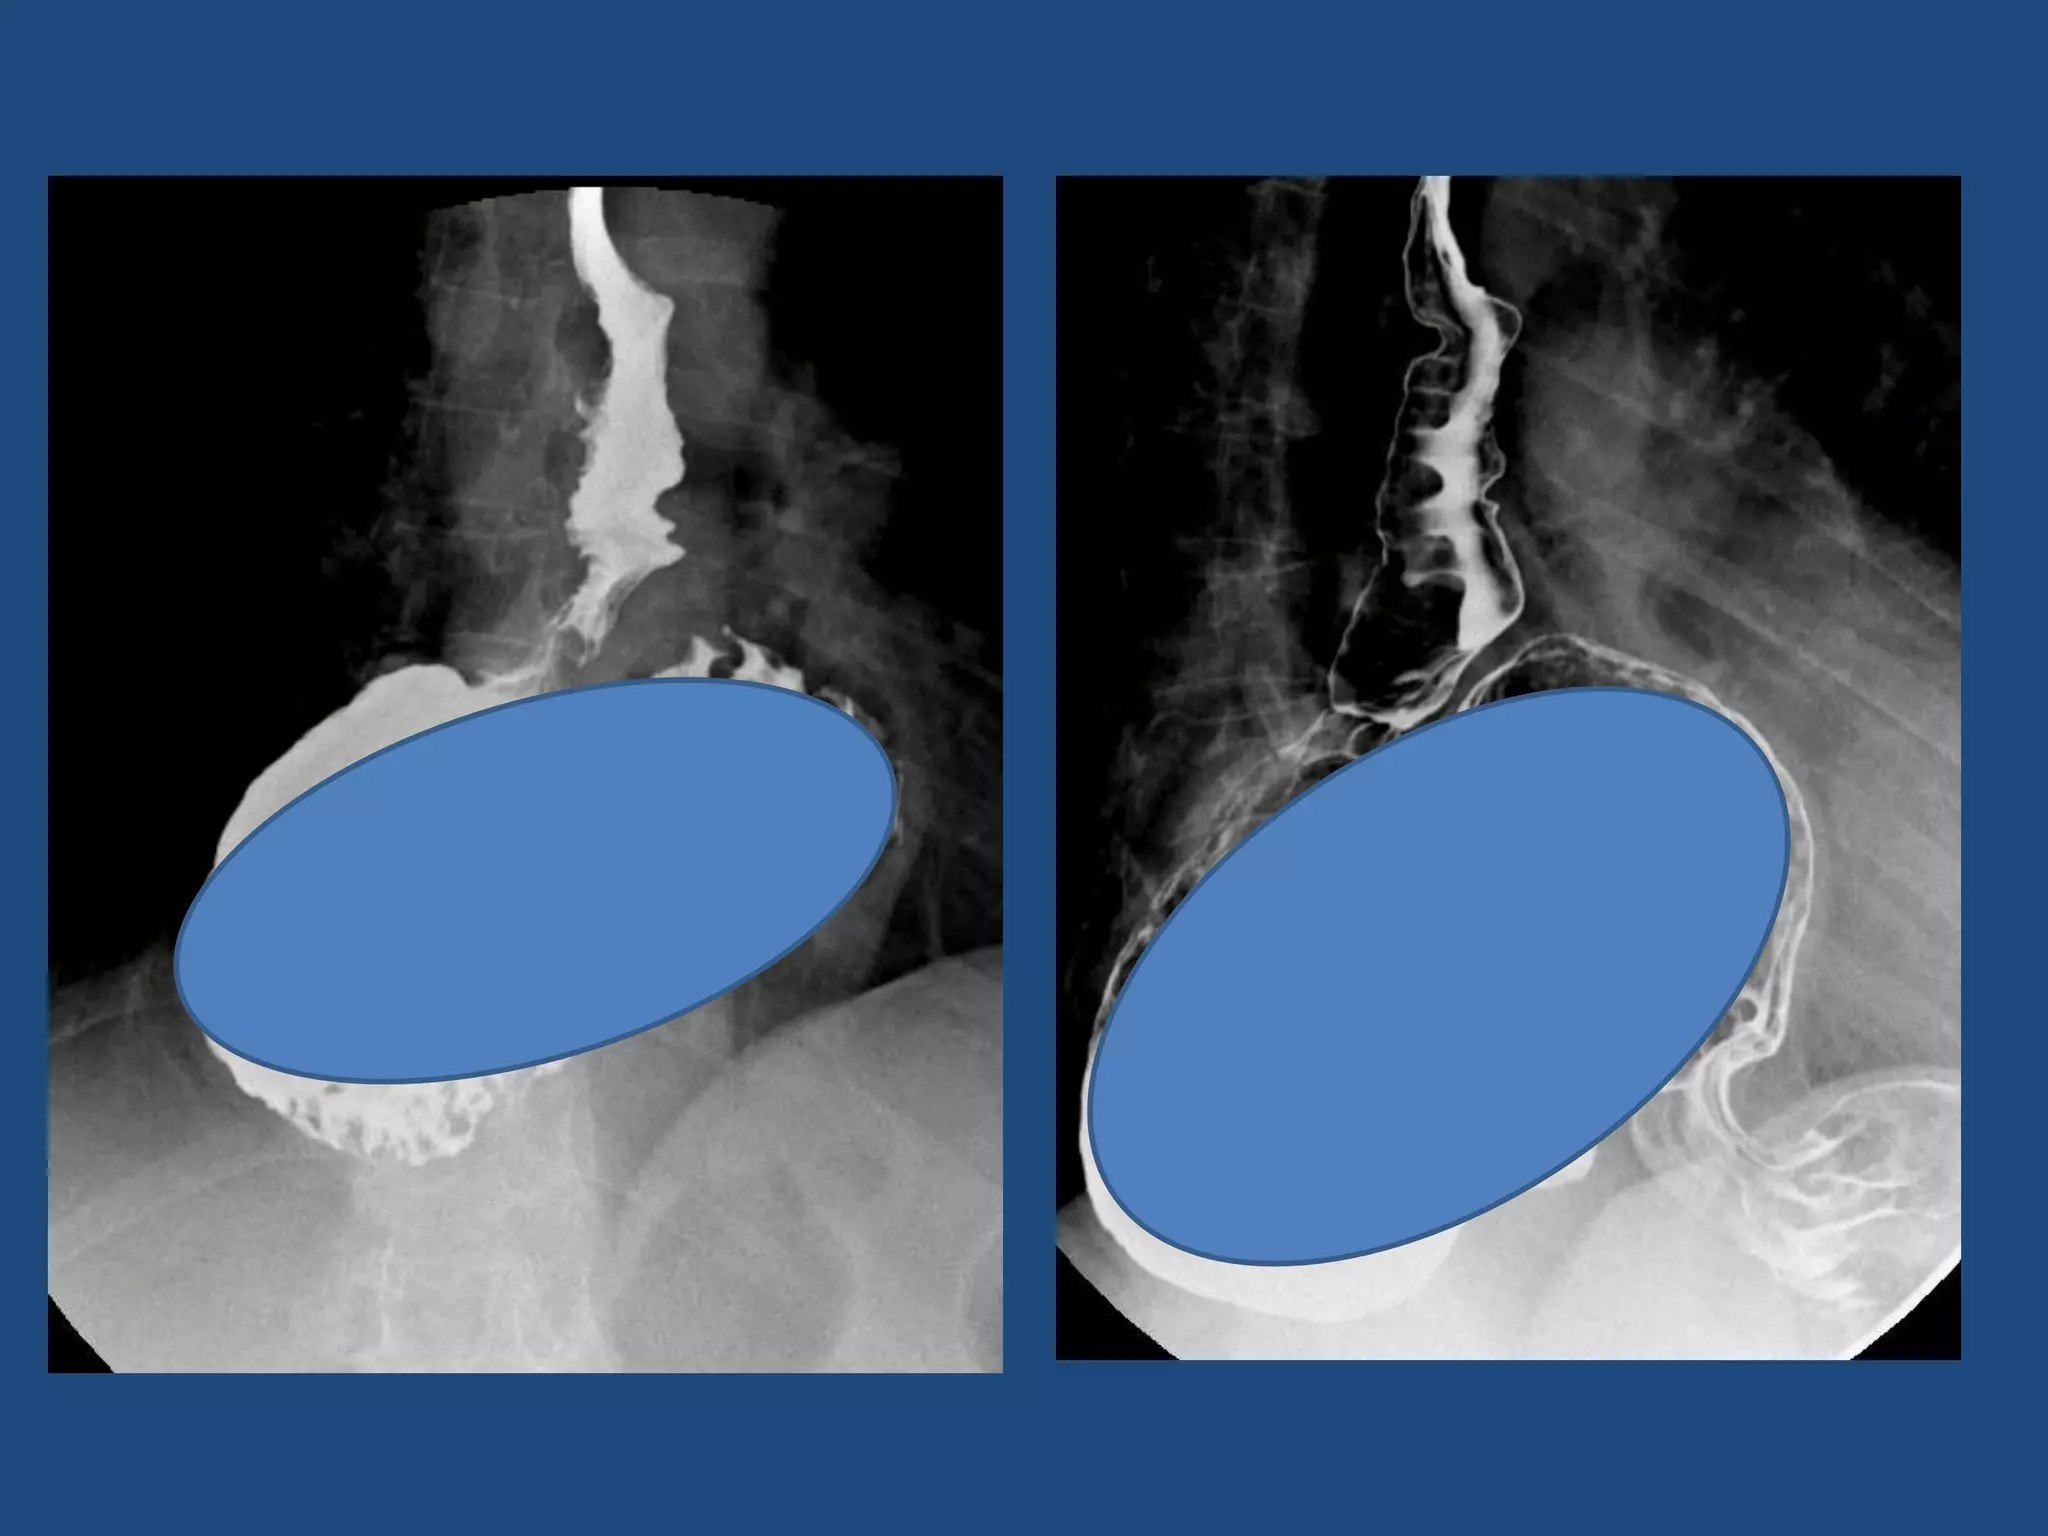

ESOFAGO: HERNIA HIATAL

• Ascenso parcial o total del estomago al tórax

• Principal factor predisponente de RGE

• Hallazgo :

- Ascenso visceral

HH

RGE